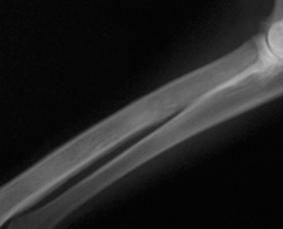

Figura 1. Câine. Radiografie membrul anterior stâng, regiunea antebrațului, incidență latero-laterală. Semne de neomogenitate a matricei osoase (radius), aspect de fum de țigară – panosteită. Radiografie realizată în sistem clasic

în comerț monitoare dedicate pentru imaginile medicale care au o rezoluție crescută. Acest tip de imagini poate fi supus procedurilor de prelucrare post-procesare pentru analiza cantitativă a conținutului informativ, pentru evaluări morfometrice (dimensiuni liniare, unghiuri, suprafață), pentru reconstrucții 3D (fig. 3).

Figura 2. Detaliu al figurii 1